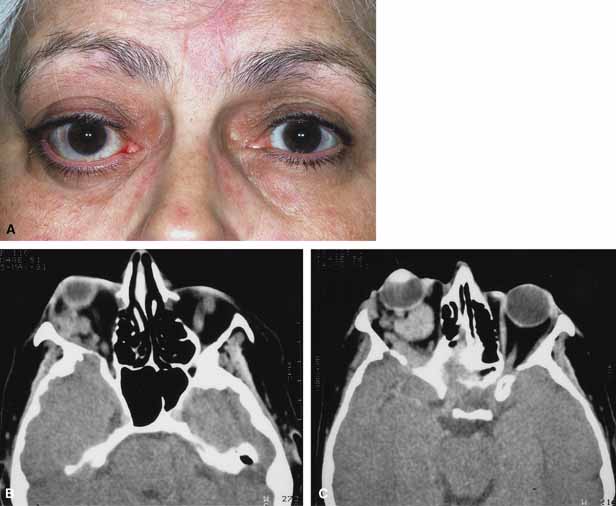

Trauma is one of the numerous causes of orbital hemorrhage. Hemorrhage may be localized and of little consequence, diffuse or subperiosteal and compromise optic nerve function.100–102 Management is dependent on the extent of visual compromise. Orbital hemorrhage without visual compromise will resolve without treatment. Accumulation of blood within the confined orbital space may also form a hematoma. Orbital hematomas can be classified as intraorbital or subperiosteal. Intraorbital hematomas are more common and include the characteristic findings of lid ecchymosis, lid edema, axial globe displacement, diffuse subconjunctival hemorrhage, restricted ocular motility, and varying degrees of visual dysfunction (Fig. 7A, 7B, and 7C). Subperiosteal hematomas are less common and the characteristic findings include proptosis, downward globe displacement, lid ecchymosis, motility impairment, and varying degrees of visual dysfunction. Subperiosteal hematomas most often occur acutely after orbital trauma but may also present days later (Fig. 15A, 15B, and 15C). They more commonly involve the roof and are secondary to rupture of the subperiosteal blood vessels or extrusion of a subgaleal hematoma with subsequent accumulation of blood between the underlying bone and periosteum.104 Nontraumatic subperiosteal orbital hemorrhages (i.e., spontaneous, after straining, vomiting, childbirth, scuba diving, etc.) may also occur, although uncommon.62,63 Similar to the traumatic ones they more commonly occur superiorly.

Fig. 15 A. A 19-year-old university student fell 10–15 feet from a parking garage. While in the emergency department he developed eyelid ecchymosis and reduced visual acuity of the left eye. B. Axial computed tomography (CT) scans revealed a subperiosteal hematoma posteriorly along the medial orbital wall. The blood was drained and postoperatively the acuity returned to 20/20. C. Axial computed tomography (CT) scans revealed a subperiosteal hematoma posteriorly along the medial orbital wall. The blood was drained and postoperatively the acuity returned to 20/20.

The diagnosis of intraorbital or subperiorbital hematoma is made with imaging. CT typically shows a well-defined nonenhancing mass. The presence or absence of orbital wall fracture can be visualized easily. Subperiosteal and orbital hematomas can regress without treatment. When visual compromise is present, rapid evacuation of the hematoma is recommended. Both orbital exploration with drainage of the hematomas and needle aspiration have been described.104–108 Advantages of orbital exploration and drainage include the ability to remove coagulated blood, cauterize any active bleeding, place a drain at the wound site, and repair associated fractures. Needle aspiration is technically easier to perform and does not require operating room time. However, its limitations include rebleeding and the inability to remove clotted blood.